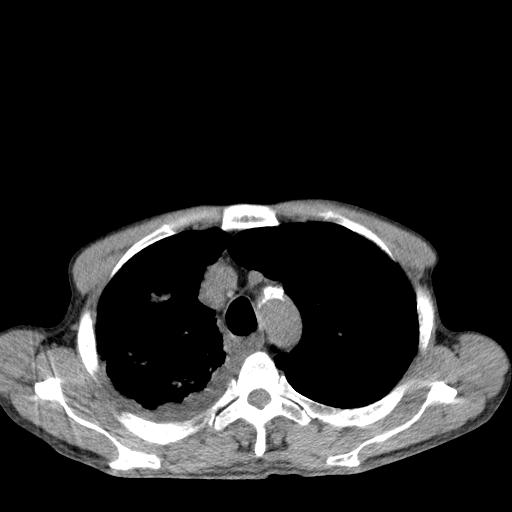

男性 75  咳嗽 一周前发热最高达39

右肺继发型tb并右侧tb性胸腔炎,右侧胸腔大量积液并右下肺膨胀不全,慢支肺气肿、多发肺大泡。建议抽胸水实验室检查并复查排除恶性在占位。

右上肺继发型肺结核,右胸腔中等量积液。

结核的基础上有纵隔淋巴结肿大,右侧有胸水,但右侧纵隔反而窄,说明有肺有不张。

再就是右下肺有块影,和不张混合,还是不能除外肺癌。

补充材料,患者2月份ct片大致正常,双侧胸腔积液,2月份抽胸水未发现ca细胞,现患者发热,痰多,各气管通畅,

1)右肺继发型肺结核。2)左肺胸膜下多发性肺大泡。3)右侧胸腔积液。